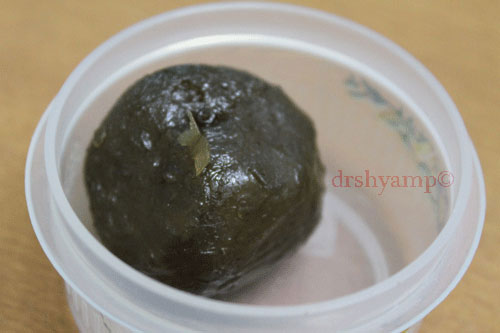

Amlas (Indian gooseberries) are a major ingredient in several herbal tonics as they are reputed to be good for the liver, eyes and stomach. Amlas are the richest known source of vitamin C. The Sweet Amla candy is prepared by soaking 1/2 kg (10-12 pieces) of the fruit in a syrup containing 350gms of sugar. The candy is either chewed or allowed to stay in the mouth. Chewing and swallowing does not allow the sugar to come in contact with the teeth for a long time. However, keeping the candy in the mouth for a prolonged amount of time creates an acidic environment in the oral cavity. This causes the demineralization of the tooth causing it to eventually decay.